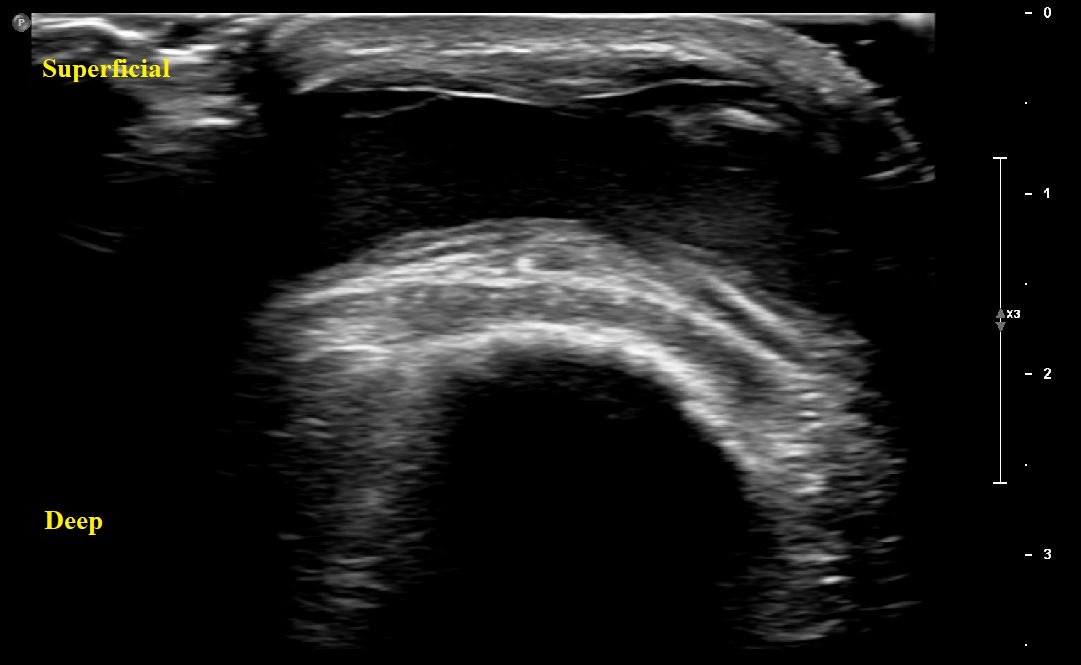

Short Axis view of Right proximal patellar tendon showing large complex fluid within the prepatellar bursa with bursal lining hypertrophy at the base.

Short Axis view of proximal patellar tendon with overlying prepatellar bursal distension.